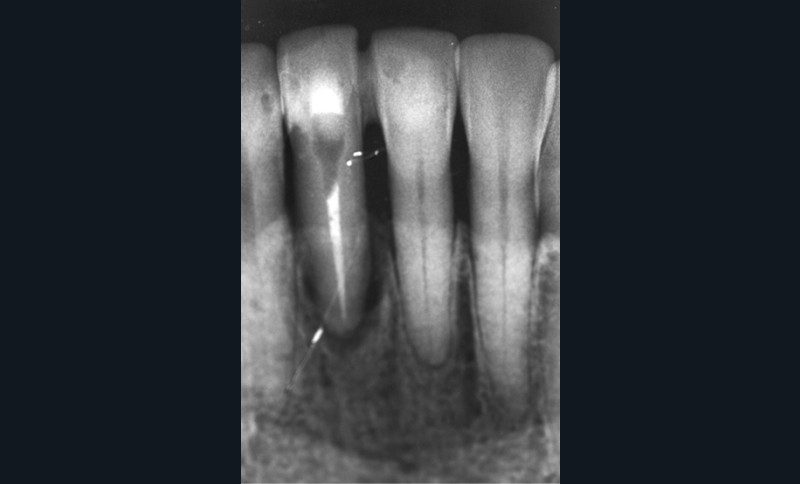

Le cas clinique présenté dans cet article traite de la gestion d’un édentement mandibulaire dans le secteur antérieur, survenu après un accident de la voie publique ayant entraîné une aggravation d’une lésion parodontale existante (fig. 1). Cette pathologie a nécessité l’extraction de la dent qui avait été traitée huit ans auparavant par une attelle-bridge en zircone, compte tenu de l’impossibilité médicale de mettre en place un implant (fig. 2).